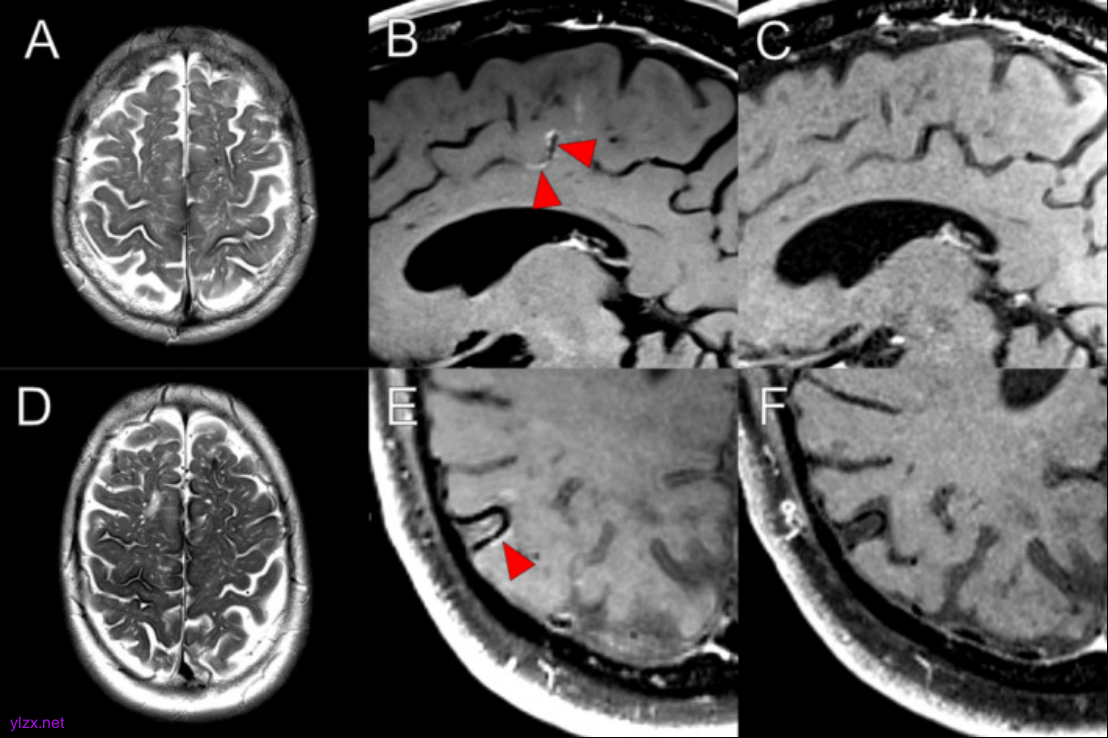

图1.每列包含情况 1 到 4 的磁共振图像

使用 VWI 的高分辨率造影剂后 MRI,在 6 名持续性 CAA 相关 TFNE 患者中描述了软脑膜、实质和小皮质动脉壁增强的各种组合,与短暂性炎症一致。在 6 例病例中的 5 例中,增强包括与解剖学上与 TFNE 症状相关的区域,尽管增强通常相当弥漫,以后(顶枕)为主。这些观察结果表明,炎症可能在持续性 CAA 相关 TFNE 的病理生理学中发挥作用,并且可能在更普遍的 CAA 中发挥作用。

钆造影剂后脑部 MRI 和高分辨率血管壁成像 (vessel wall imaging,VWI) 提供了一种非侵入性方法来评估单个小血管内的血脑屏障 (blood–brain barrier,BBB) 破坏和血管病变变化。1月8日,伦敦大学 David J Werring教授团队在Annals of Neurology(IF=8.1)在线发表了题为“Inflammation in Cerebral Amyloid Angiopathy-Related Transient Focal Neurological Episodes”的研究,描述了 6 名持续性 CAA 相关 TFNE 患者,其中钆后 MRI 发现与小血管、软脑膜和脑实质急性炎症一致的异常。